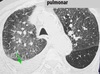

Homem, 30 anos, febre e tosse há 2 dias. Anosmia há 6 horas. Qual diagnóstico?

COVID-19